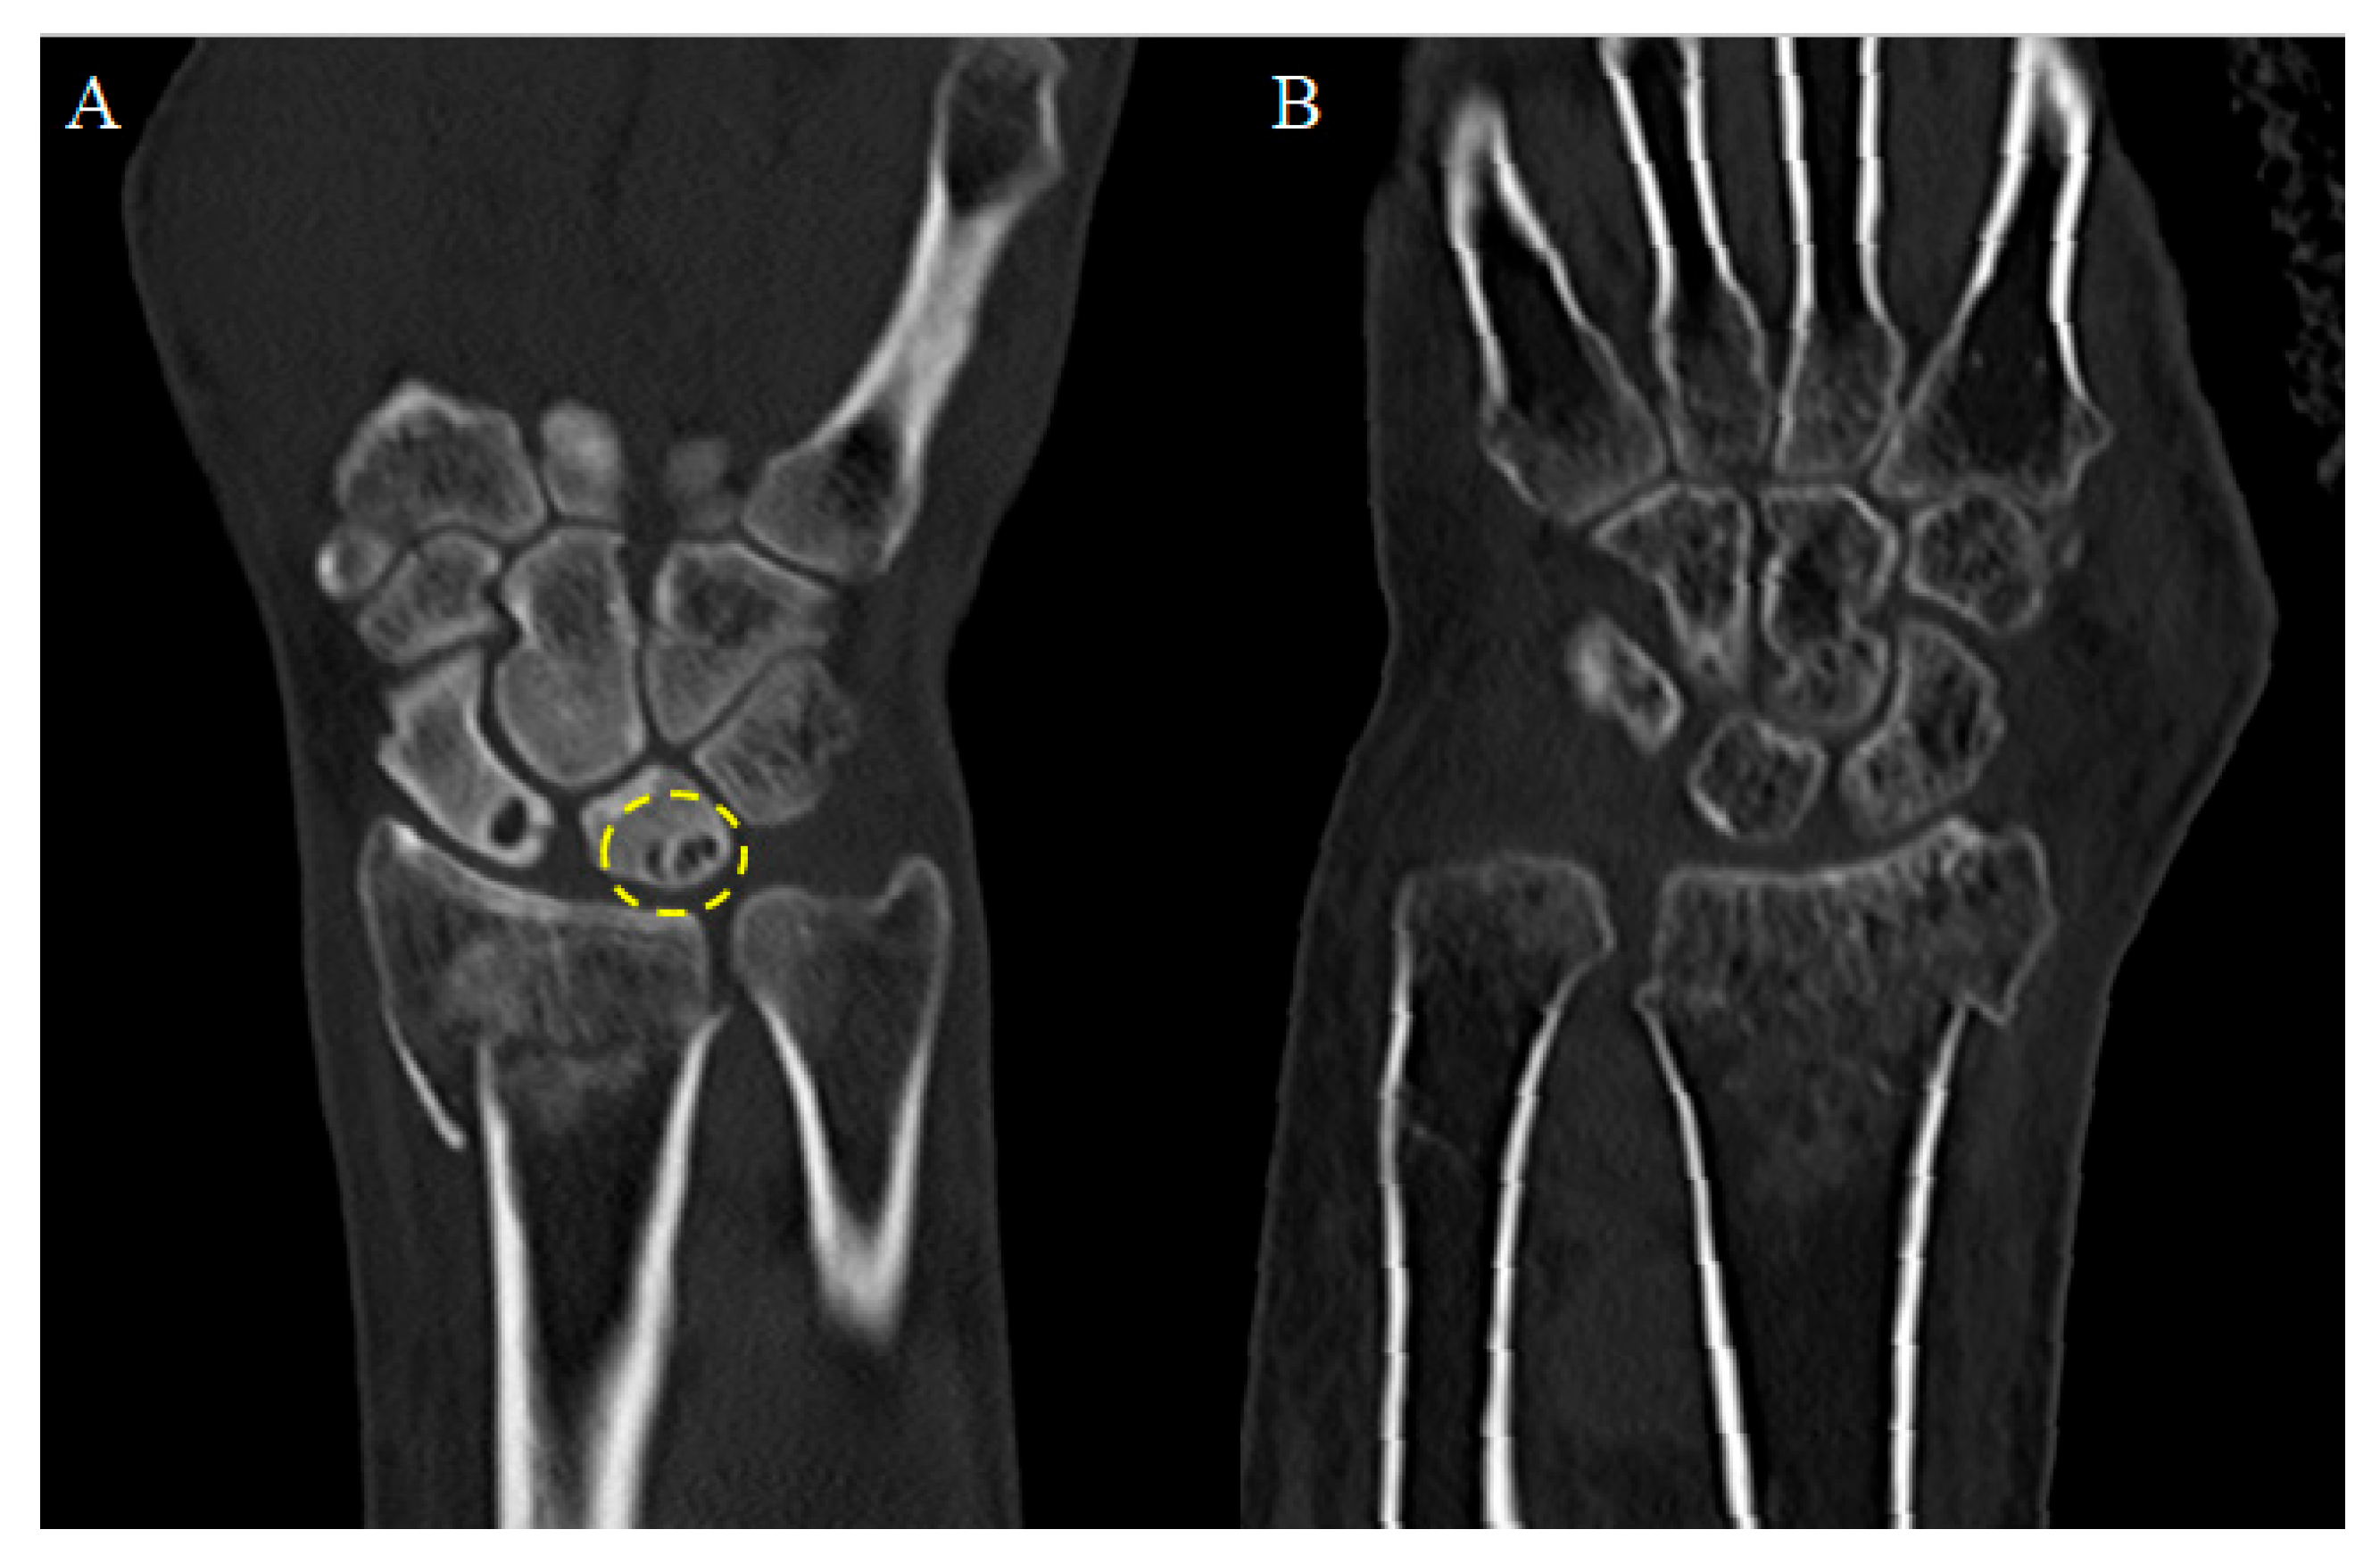

Highinter-observer reliability was confirmed, as there were no statistically significant differences between the radiological measurements performed by the two residents; therefore, the mean values were used for the final analysis. As can be seen in (Table 2),In the cyst group, the mean ulnar variance increased from 0.592 mm immediately postoperatively to 0.783 mm at the final follow-up, but this change was not statistically significant (p = 0.181). Conversely, the ulnolunate distance in the cyst group significantly decreased from 4.790 mm to 3.799 mm during the follow-up period (p< 0.001). Statistical significance was defined as a two-sided p-value < 0.05. Similarly, the control group showed an increase in mean ulnar variance from 0.769 mm to 1.002 mm without statistical significance (p = 0.068), while the ulnolunate distance significantly decreased from 4.648 mm to 3.525 mm (p = 0.001). Crucially, when comparing the magnitude of change (delta) between the two groups, there were no statistically significant differences in either ulnar variance or ulnolunate distance. (Table 3) Representative preoperative CT images for the cyst(+) and cyst(–) groups are shown for direct comparison (Figure 4). Regarding the anatomical location of the cysts, 21 patients (75%) had cysts on the dorsal side, 4 patients (14%) on the palmar side, and 3 patients (11%) were classified as indeterminate. (Table 4) Thus, dorsal side cysts were predominant in our study population.

Figure 4. Representative preoperative CT images of patients with and without lunate ulnar corner subchondral cysts. (A) Example of a lunate ulnar corner subchondral cyst. (B) Representative image from the cyst(–) group showing no subchondral cyst at the lunate ulnar corner.

Surgeries 07 00039 g004